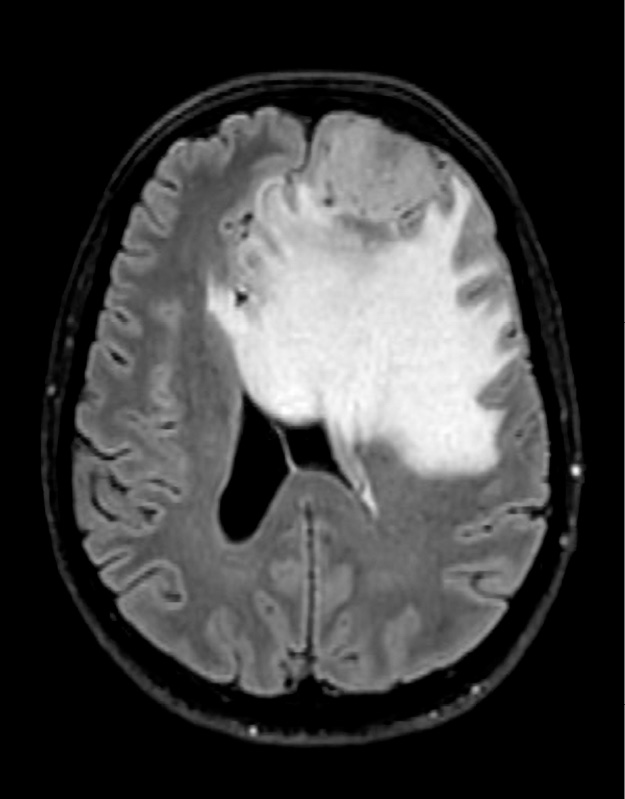

Figuur 1. Patiënte A, ongeveer 1 maand voor de operatie: meningeoom links frontaal, oedeem met massawerking

Gezien de aanhoudende klachten werd er een neuropsychologisch onderzoek (NPO) afgenomen, waarna er een magnetic resonance imaging(MRI)-scan werd verricht. Gegevens van de uitslag van het NPO waren niet beschikbaar, doordat het voortraject in een ander ziekenhuis had plaatsgevonden. De scan toonde een afwijking links frontaal met peritumoraal oedeem, die het meest deed denken aan een meningeoom WHO-graad I.